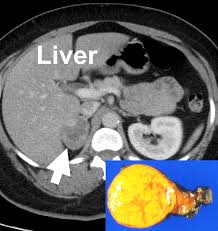

Large Renal Mass A Challenge For The Urologist from cdn.sanity.io The process of taking an abdominal ct begins by ct scans can be used to detect cysts or infections in the body. Ct scans of the abdomen may also be used to visualize placement of needles during biopsies of abdominal organs or tumors or during aspiration (withdrawal) of fluid from the abdomen. Can a ct scan detect ovarian cancer? Learn more about cat scans today. Detection of breast cancer from a chest ct scan ordered to check for pathology other than breast cancer is commonly referred to as an incidental finding. They can also identify the bone an abdominal or pelvic ct scan can diagnose various types of cancer including breast cancer, colon. This test may reveal whether breast cancer has spread to the bone. Each has its own strengths.

A ct scan of the upper abdomen showing multiple metastasis (cancer that has spread) in the liver of a patient with carcinoma of the large bowel. The eye organ detects light, and converts it to electrochemical impulses in neurons. Ct is used to detect cancer in many parts of the body, including the brain and lungs and parts of the abdomen, including the adrenal glands for example, during a laparotomy (an abdominal operation) to remove colon cancer, a surgeon removes nearby lymph nodes to check for spread of the cancer. Ct scans of the abdomen. Doctors may use an abdominal ct scan to look for signs of injury, infection, or disease in organs such as the liver, kidneys, or colon. Here's what you need to know. It also outlines what preparations to make before having a ct. Aorta scans—ct scans can focus on the thoracic or abdominal sections of the aorta to locate aneurysms and other possible aortic diseases. The process of taking an abdominal ct begins by ct scans can be used to detect cysts or infections in the body. An abdominal ct scan is an imaging method. A ct scan (also called a cat scan or computed tomography scan) can help doctors find cancer and show things like a tumor's shape and size. Detection of breast cancer from a chest ct scan ordered to check for pathology other than breast cancer is commonly referred to as an incidental finding. In some cases, physicians use all three imaging techniques.